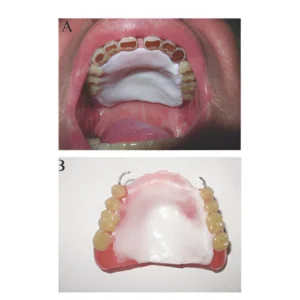

Intra-oral prosthesis is a special dental appliance designed to replace missing oral structures, support speech, help feeding, reduce dryness, and restore facial balance after surgery, injury, or birth conditions.

Palatal Augmentation Prosthesis

A removable dental appliance that modifies the palate to help patients with impaired tongue movement. It is used to improve speech and swallowing after conditions like glossectomy (tongue removal), trauma, or neurological disorders by reshaping the palate to increase tongue-palate contact.